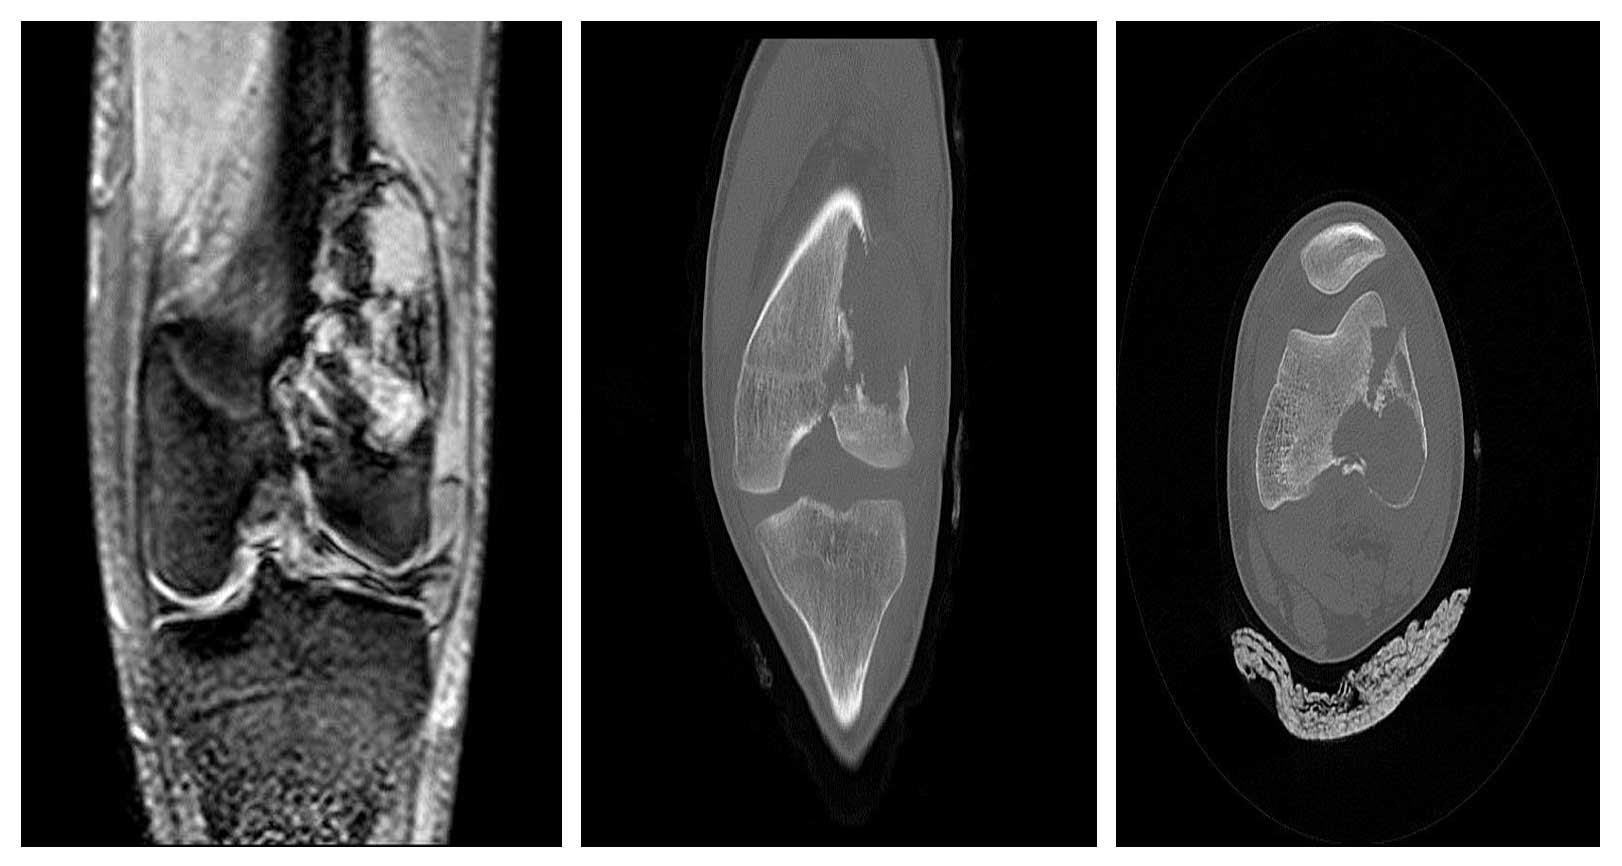

Vaka 30: Diz (Distal femur) Yerleşimli Osteosarkom

Distal femurda osteosarkoma bağlı gelişen patolojik kırık sonrası kemoterapi ve cerrahi tedavi uygulanan genç erkek hastamızda, tümörün tamamen çıkarılması ve diz fonksiyonlarının korunması hedeflenmiştir.

Distal femur yerleşimli osteosarkoma bağlı patolojik kırık nedeniyle başvurdu.

Ameliyat Öncesi: MR ve tomografide aynı lokalizasyonda kırığın eşlik ettiği harabiyet görülmekte.